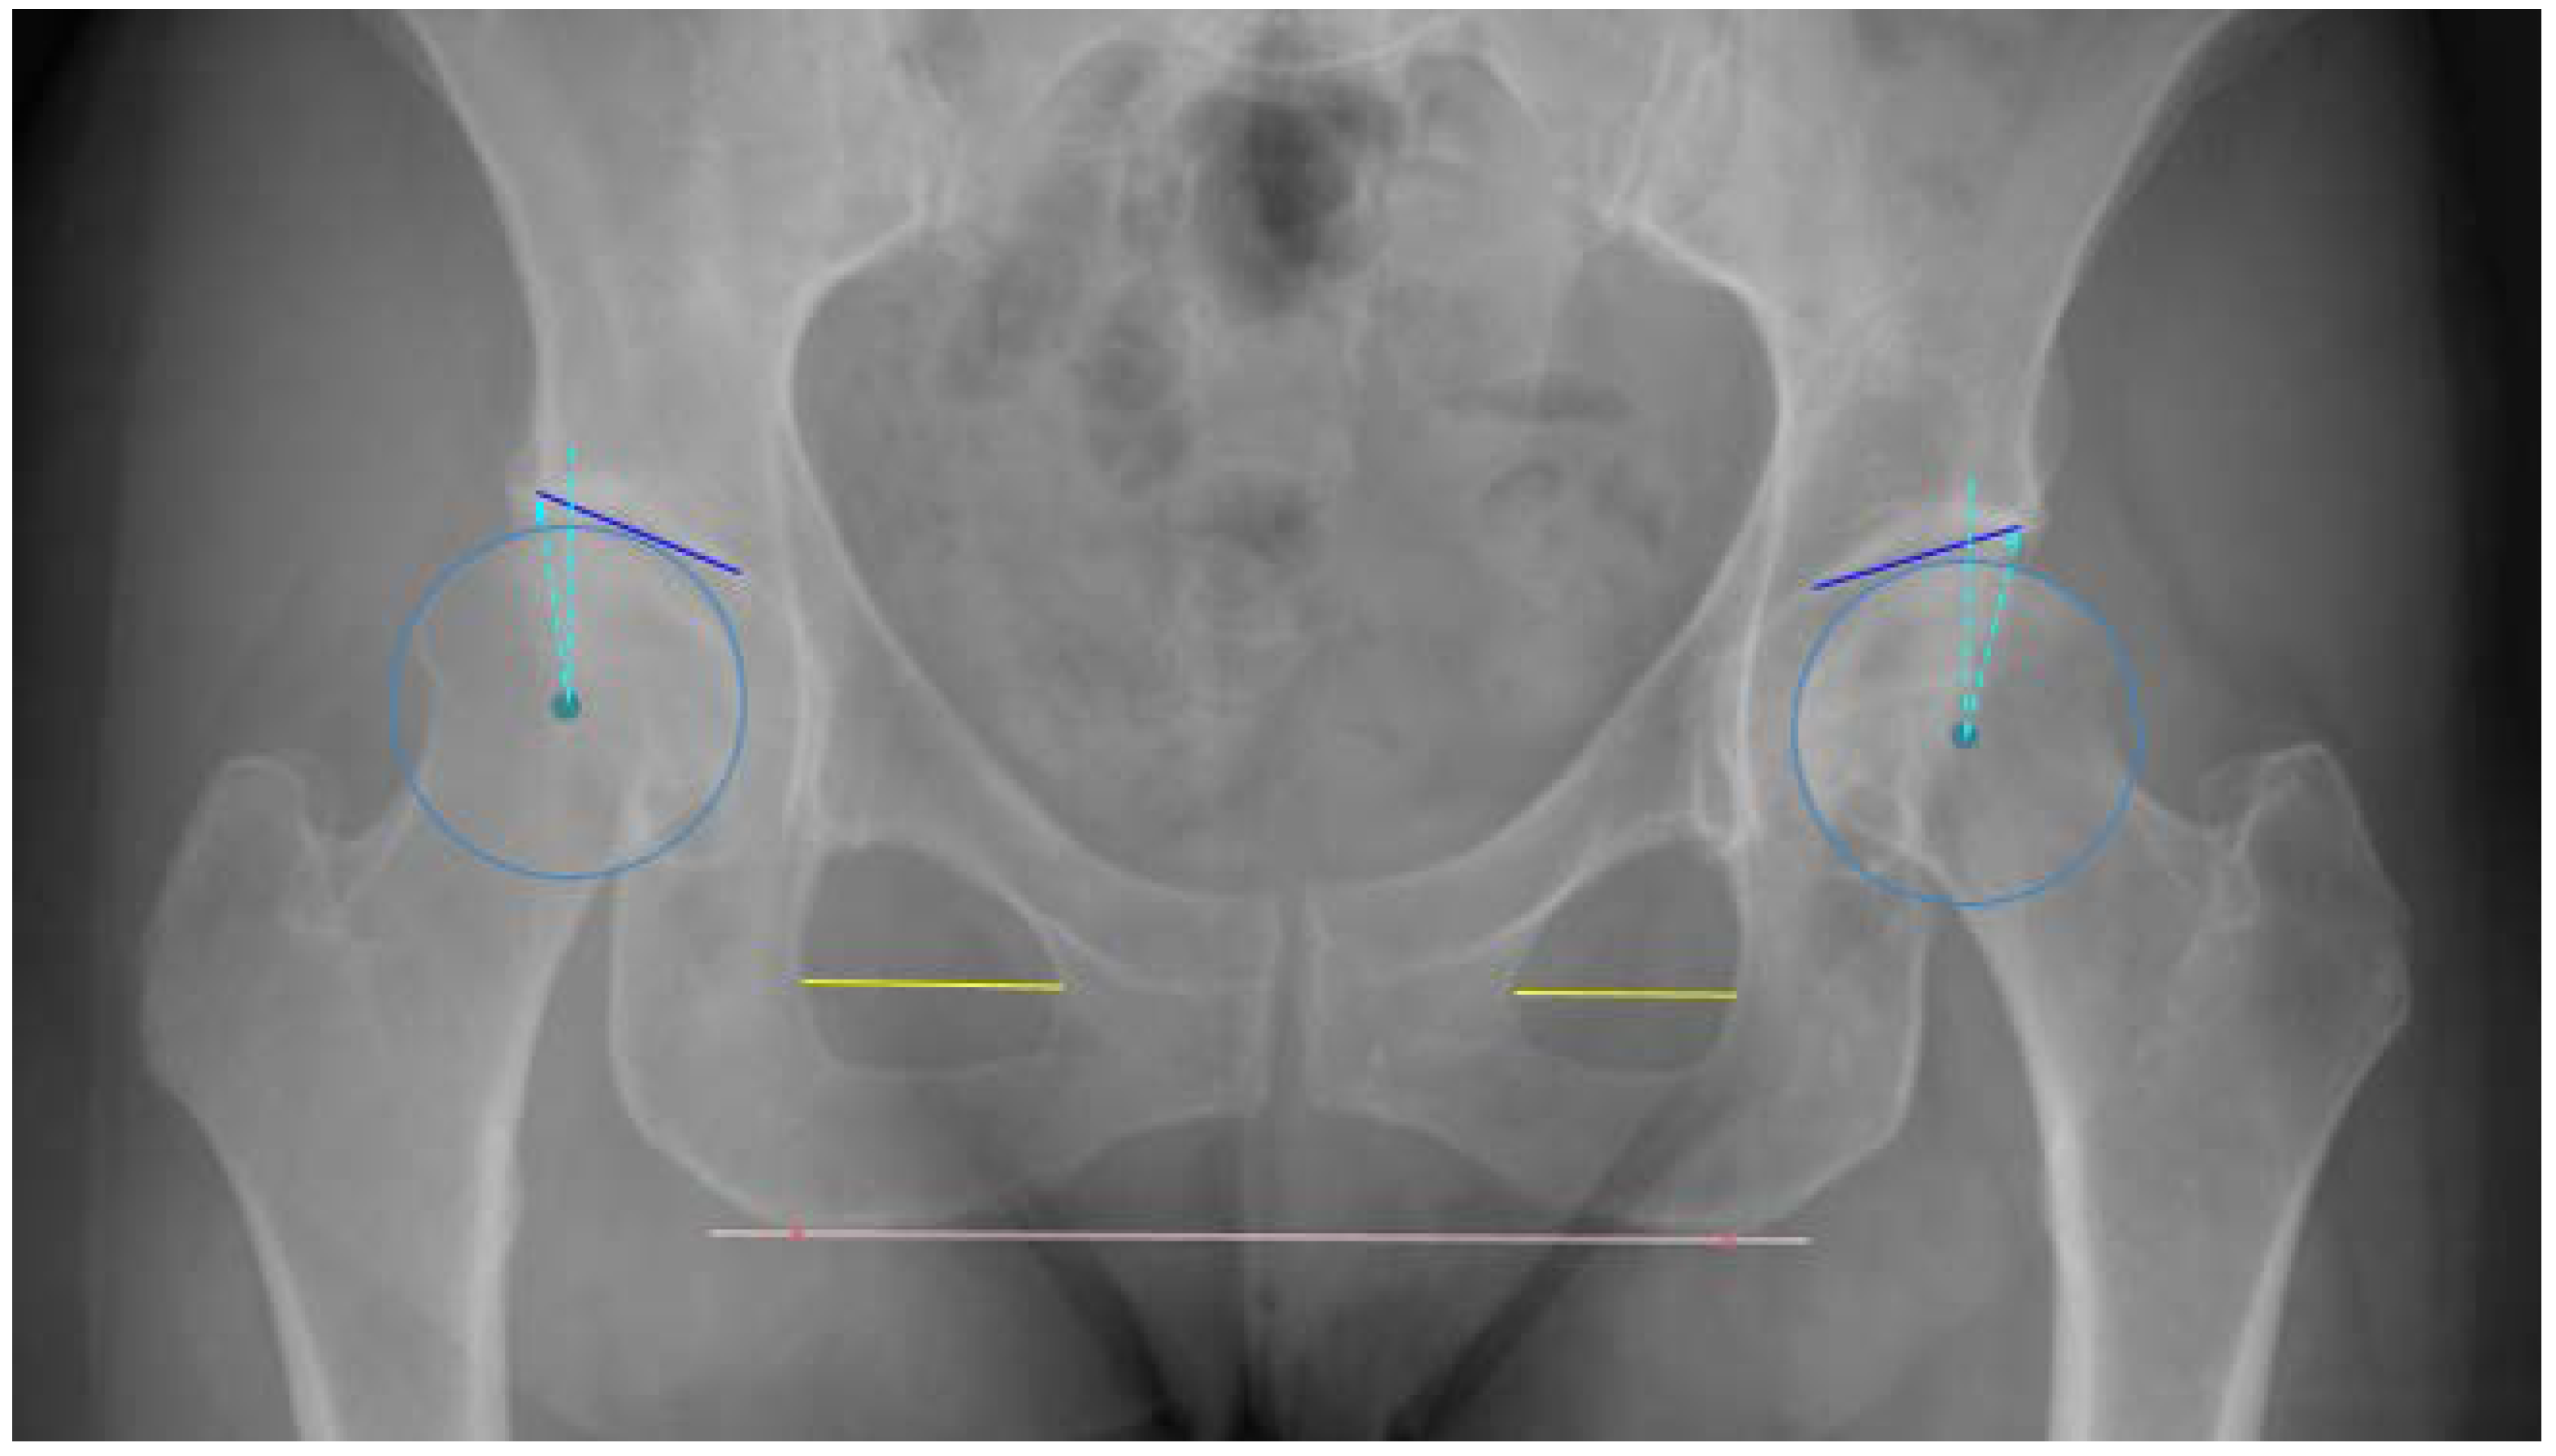

2.3. Anatomic Definitions

2.4. Algorithm Development and Training